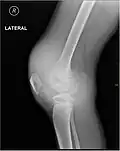

L'hémarthrose est un épanchement de sang dans une cavité articulaire consécutif d'une lésion ligamentaire, d'une fracture osseuse ou encore d'une atteinte du cartilage osseux[1]. Cette physiopathologie est caractéristique des personnes atteintes d'hémophilie sévère et dans une moindre mesure chez les formes modérées, car chez les hémophiles, l’absence ou l’altération d’un des facteurs de la coagulation (VIII ou IX selon le type d’hémophilie) perturbe le processus de la coagulation, au point qu’un traumatisme minime peut provoquer un saignement prolongé[2]